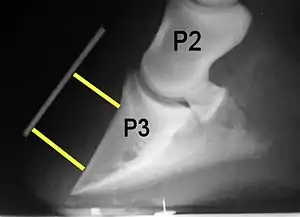

Radiographs

Radiographs are an important part of evaluating the laminitic horse. They not only allow the practitioner to determine the severity of the episode, which does not always correlate with degree of pain,[1] but also to gauge improvement and response to treatment. Several measurements are made to predict severity. Additionally, radiographs also allow the visualization and evaluation of the hoof capsule, and can help detect the presence of a lamellar wedge or seromas.[1] The lateral view provides the majority of the information regarding degree of rotation, sole depth, dorsal hoof wall thickness, and vertical deviation.[1][17] A 65-degree dorsopalmar view is useful in the case of chronic laminitis to evaluate the rim of the coffin bone for pathology.[1]

Several radiographic measurements, made on the lateral view, allow for objective evaluation of the episode.

- Horn:lamellar distance (HL): the measurement from the most superficial aspect of the dorsal hoof wall to the face of P3. 2 distances are compared: a proximal measurement made just distal to the extensor process of P3, and a distal measurement made toward the tip of P3. These two values should be similar. In cases of rotation, the distal measurement will be higher than the proximal. In cases of distal displacement, both values will increase, but may remain equal. Therefore, it is ideal to have baseline radiographs for horses, especially for those at high-risk for laminitis, to compare to should laminitis ever be suspected. Normal HL values vary by breed and age:[1]

- Weanlings will have a greater proximal HL compared to distal HL

- Yearlings will have approximately equal proximal and distal HL

- Thoroughbreds are usually 17mm proximally, and 19mm distally

- Standardbreds have been shown to have a similar proximal and distal HL, around 16 mm at 2 years old, and 20 mm at 4 years old

- Warmbloods have similar proximal and distal values, up to 20 mm each

- HL tends to increase with age, up to 17 mm in most light breeds, or higher, especially in very old animals